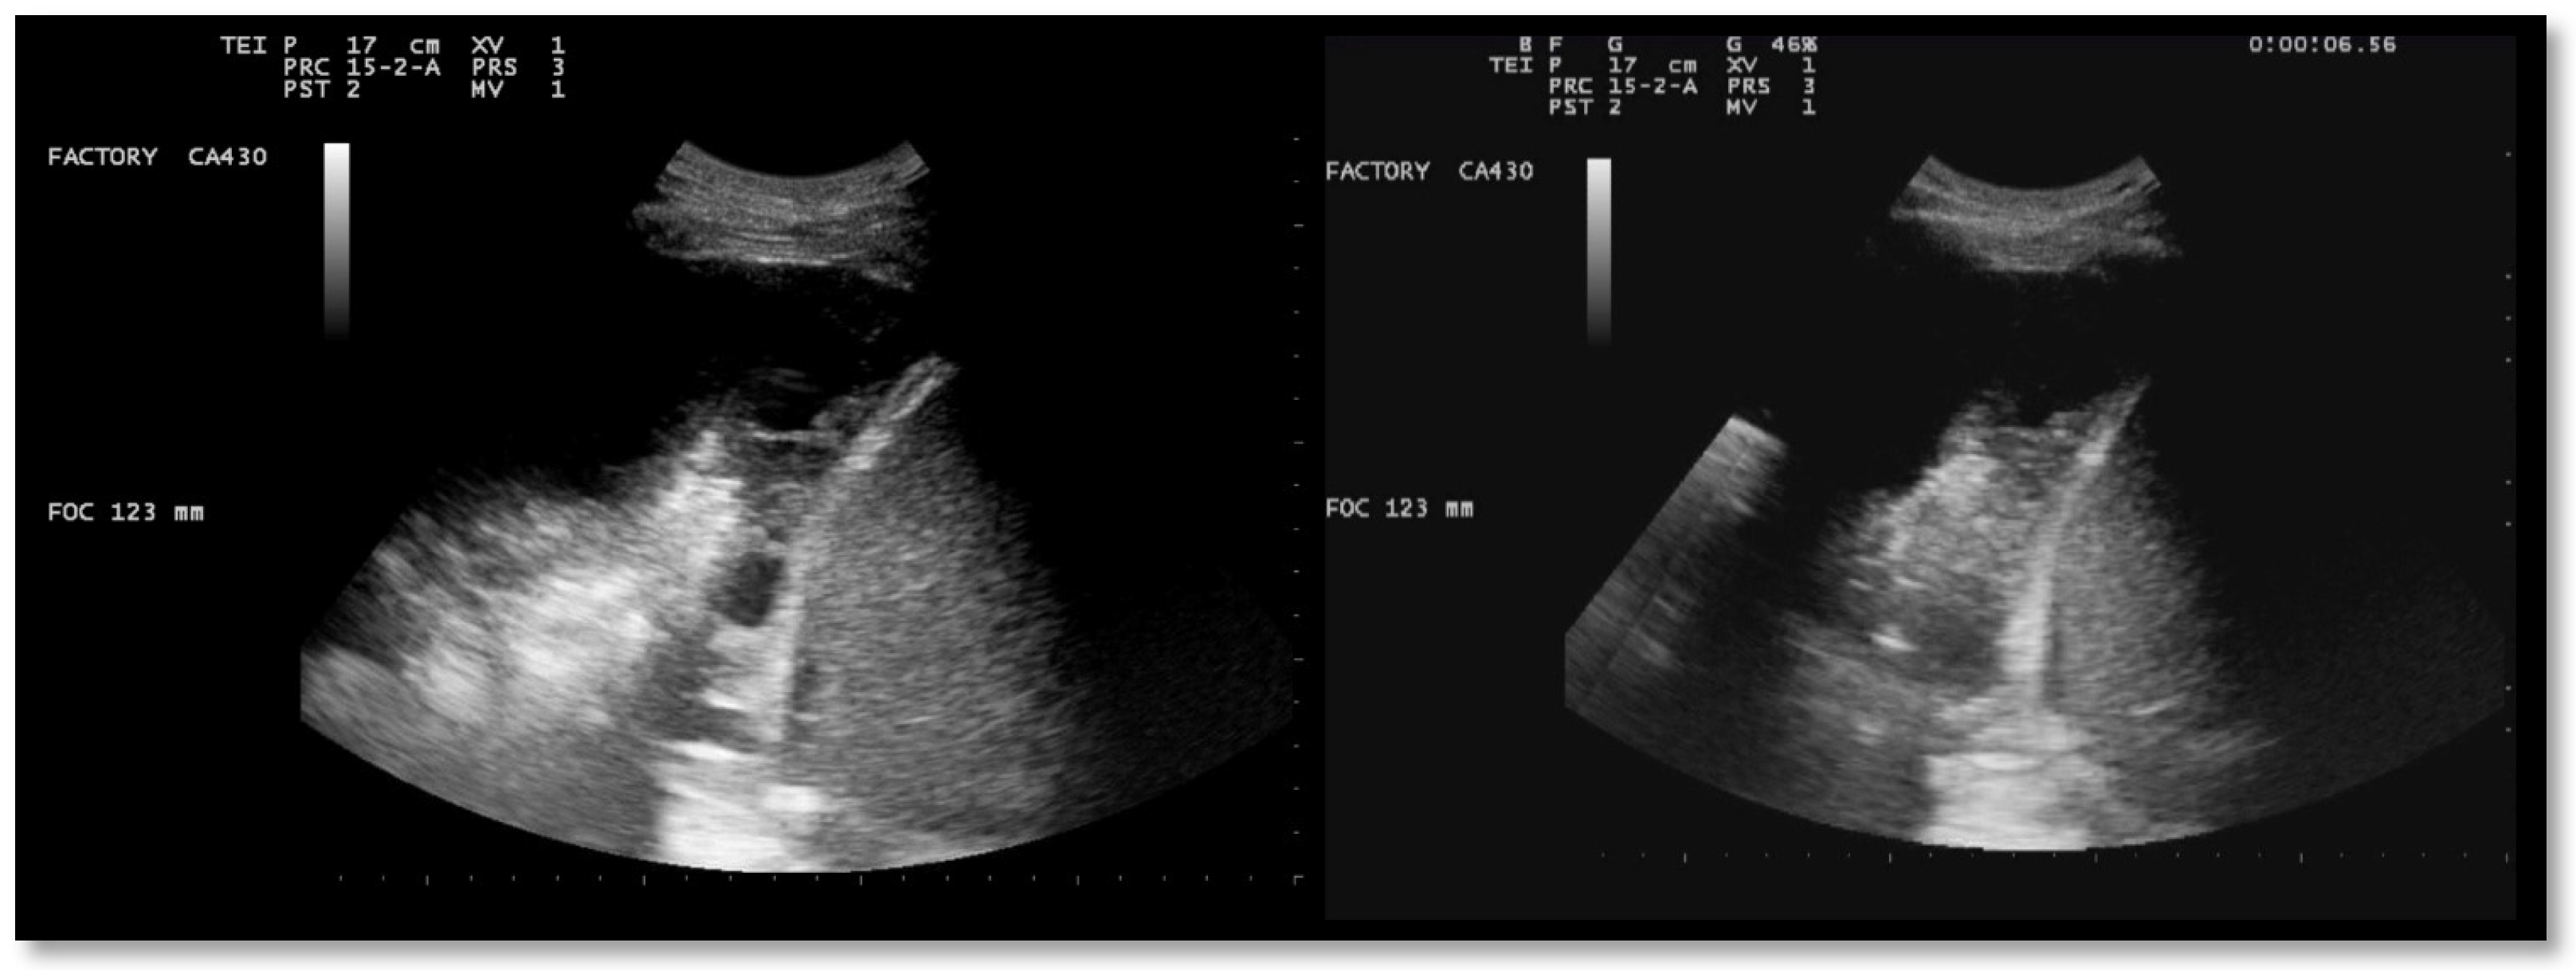

A 26-year-old man was admitted to our hospital for worsening dyspnea at rest and pain in the right hemithorax. The patient complained of a fever (39.5 °C) and productive cough for about 1 week, with mild hemoptysis in the days prior. His medical history included bilateral bronchiectasis and bronchial asthma, for which he received inhalation therapy with a long-acting antimuscarinic agent, long-acting bronchodilator, and inhaled corticosteroid. He had no family history of respiratory disease and had been tested for cystic fibrosis transmembrane regulator (CFTR) gene mutations, with negative results. The patient did not smoke cigarettes, drink alcohol, or use recreational drugs. An arterial blood gas (ABG) analysis showed acute hypoxemic normocapnic respiratory failure; therefore, oxygen therapy with a 28% FiO2 via a Venturi mask was administered. Chest radiography showed an area of opacification at the right base. Empiric antibiotic therapy with 12 mg/kg teicoplanine (Q8H) and 4.5 g piperacillin/tazobactam (Q6H) was then started on suspicion of community-acquired pneumonia. Blood tests upon his admission showed leukocytosis (WBC 18.84 × 109 cells/L) with predominant neutrophils (14.5 × 109 cells/L). Legionella and pneumococcal antigens in his urine were negative. Blood cultures after 72 h were negative. Chest ultrasonography revealed a multiloculated effusion (Figure 1).

After the placement of a chest tube, pleural fluid samples were sent for microbiological and physicochemical analysis, which confirmed the diagnosis of pleural empyema. Two days after the placement of the chest tube, the fluid flow decreased. To break up the fibrin pockets present in the empyema and promote the complete evacuation of the fluid, irrigation of the pleural cavity with 200,000 UI of urokinase in 50 mL of saline solution was performed under US guidance (Figure 2).

Immediately following the instillation of the fibrinolytic agent, the chest drain was clamped for approximately 4 h. Then, irrigation with a few ml of saline solution was performed, and the chest tube was reopened. US observations 24 h after the intrapleural fibrinolysis showed a marked reduction in the extent of the effusion and localizations (Figure 3). After 72 h, the remaining fibrin sprouts had completely disappeared (Figure 3). This facilitated the drainage of the remaining exudate. At the same time, there was an improvement in his clinical condition with the disappearance of his fever and the restoration of normal oxygenation, which led to the discontinuation of oxygen therapy.

Figure 1. Chest US at admission. Multiloculated pleural effusion.

Figure 2. Chest US during pleural lavage with urokinase. Star: distal end of chest drain; Arrow: spread of fluid.

Figure 3. Chest US 48 h (left) and 72 h (right) after intrapleural instillation of urokinase.